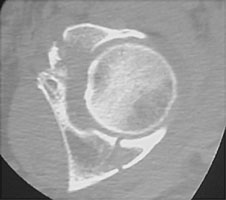

- Click on the image for a larger versionAAP radiograph of the right hip. This shows a comminuted fracture of the acetabulum.